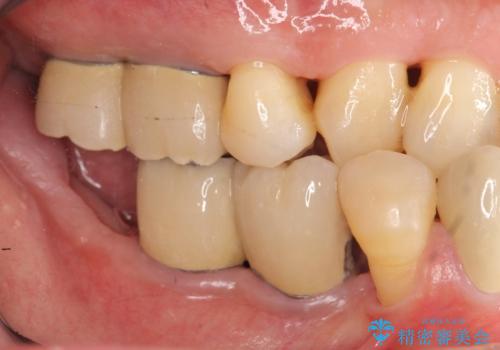

インプラント治療を併用した全顎歯周病治療

工程も多く、治療期間も長くなりがちですが、しっかりと通っていただいたおかげで安定した噛み合わせで食事を楽しむことができるようになりました。

メンテナンスも定期的に行うことで安定した状態を保っています。